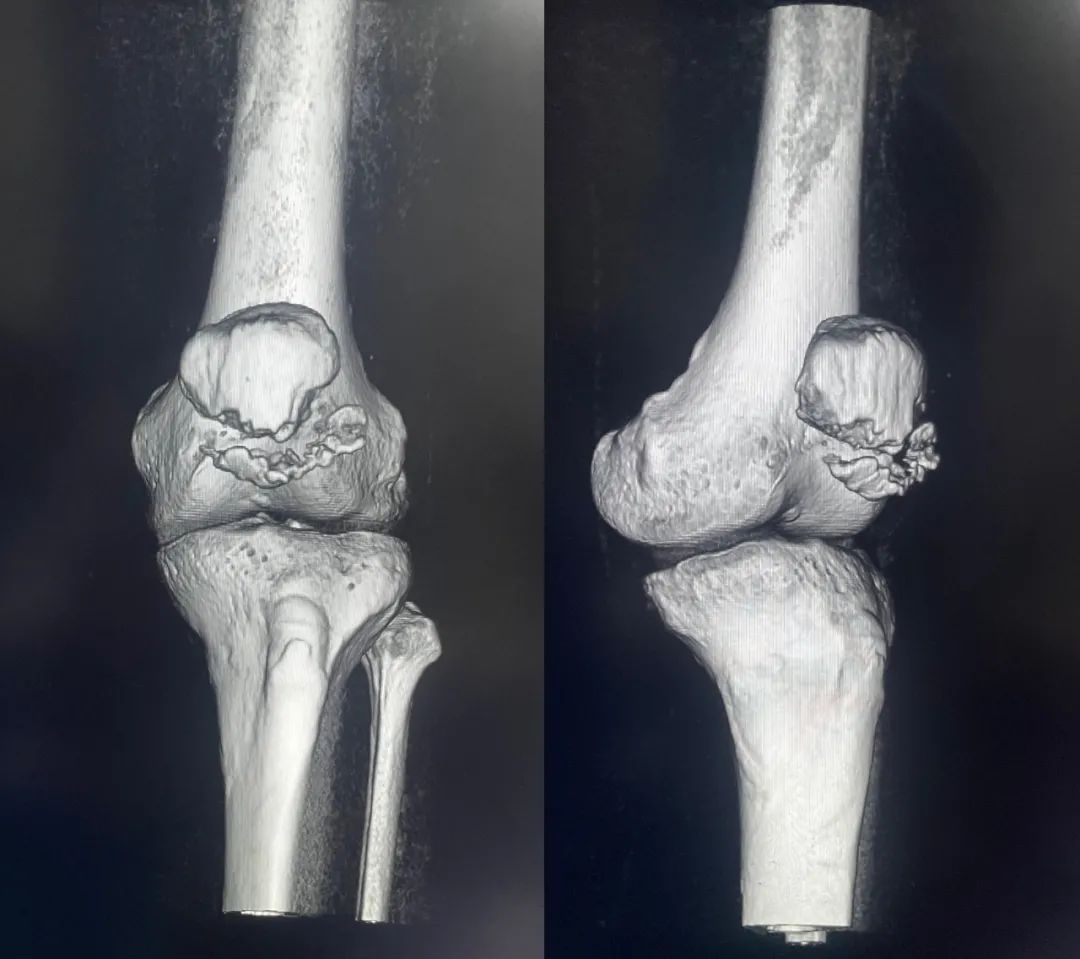

髌骨骨折正侧位  图源:作者提供

除以主诉和典型体征外,膝关节 X 线片也是必不可少的一项辅助检查,以膝关节正侧位 X 线片最常见,如果怀疑纵向骨折,膝关节屈曲 45° 时髌骨 30° 切位片可以辅助诊断。

对于骨折不愈合、畸形愈合所致的关节面不平整以及髌股关节对应关系不良可采用 CT 检查。MRI 有助于诊断软骨缺损和损伤。

完全关节内骨折克氏针加张力带固定  图源:作者提供

克氏针加张力带钢丝;有第三个骨折块则采用拉力螺钉或克氏针加张力带钢丝固定;对于 4 个或 4 个以上的骨折块采用克氏针加螺钉加张力带钢丝进行固定;对于严重粉碎和软骨面广泛破坏的髌骨骨折,髌骨部分或完全切除也是一种可行的办法。

图源:作者提供